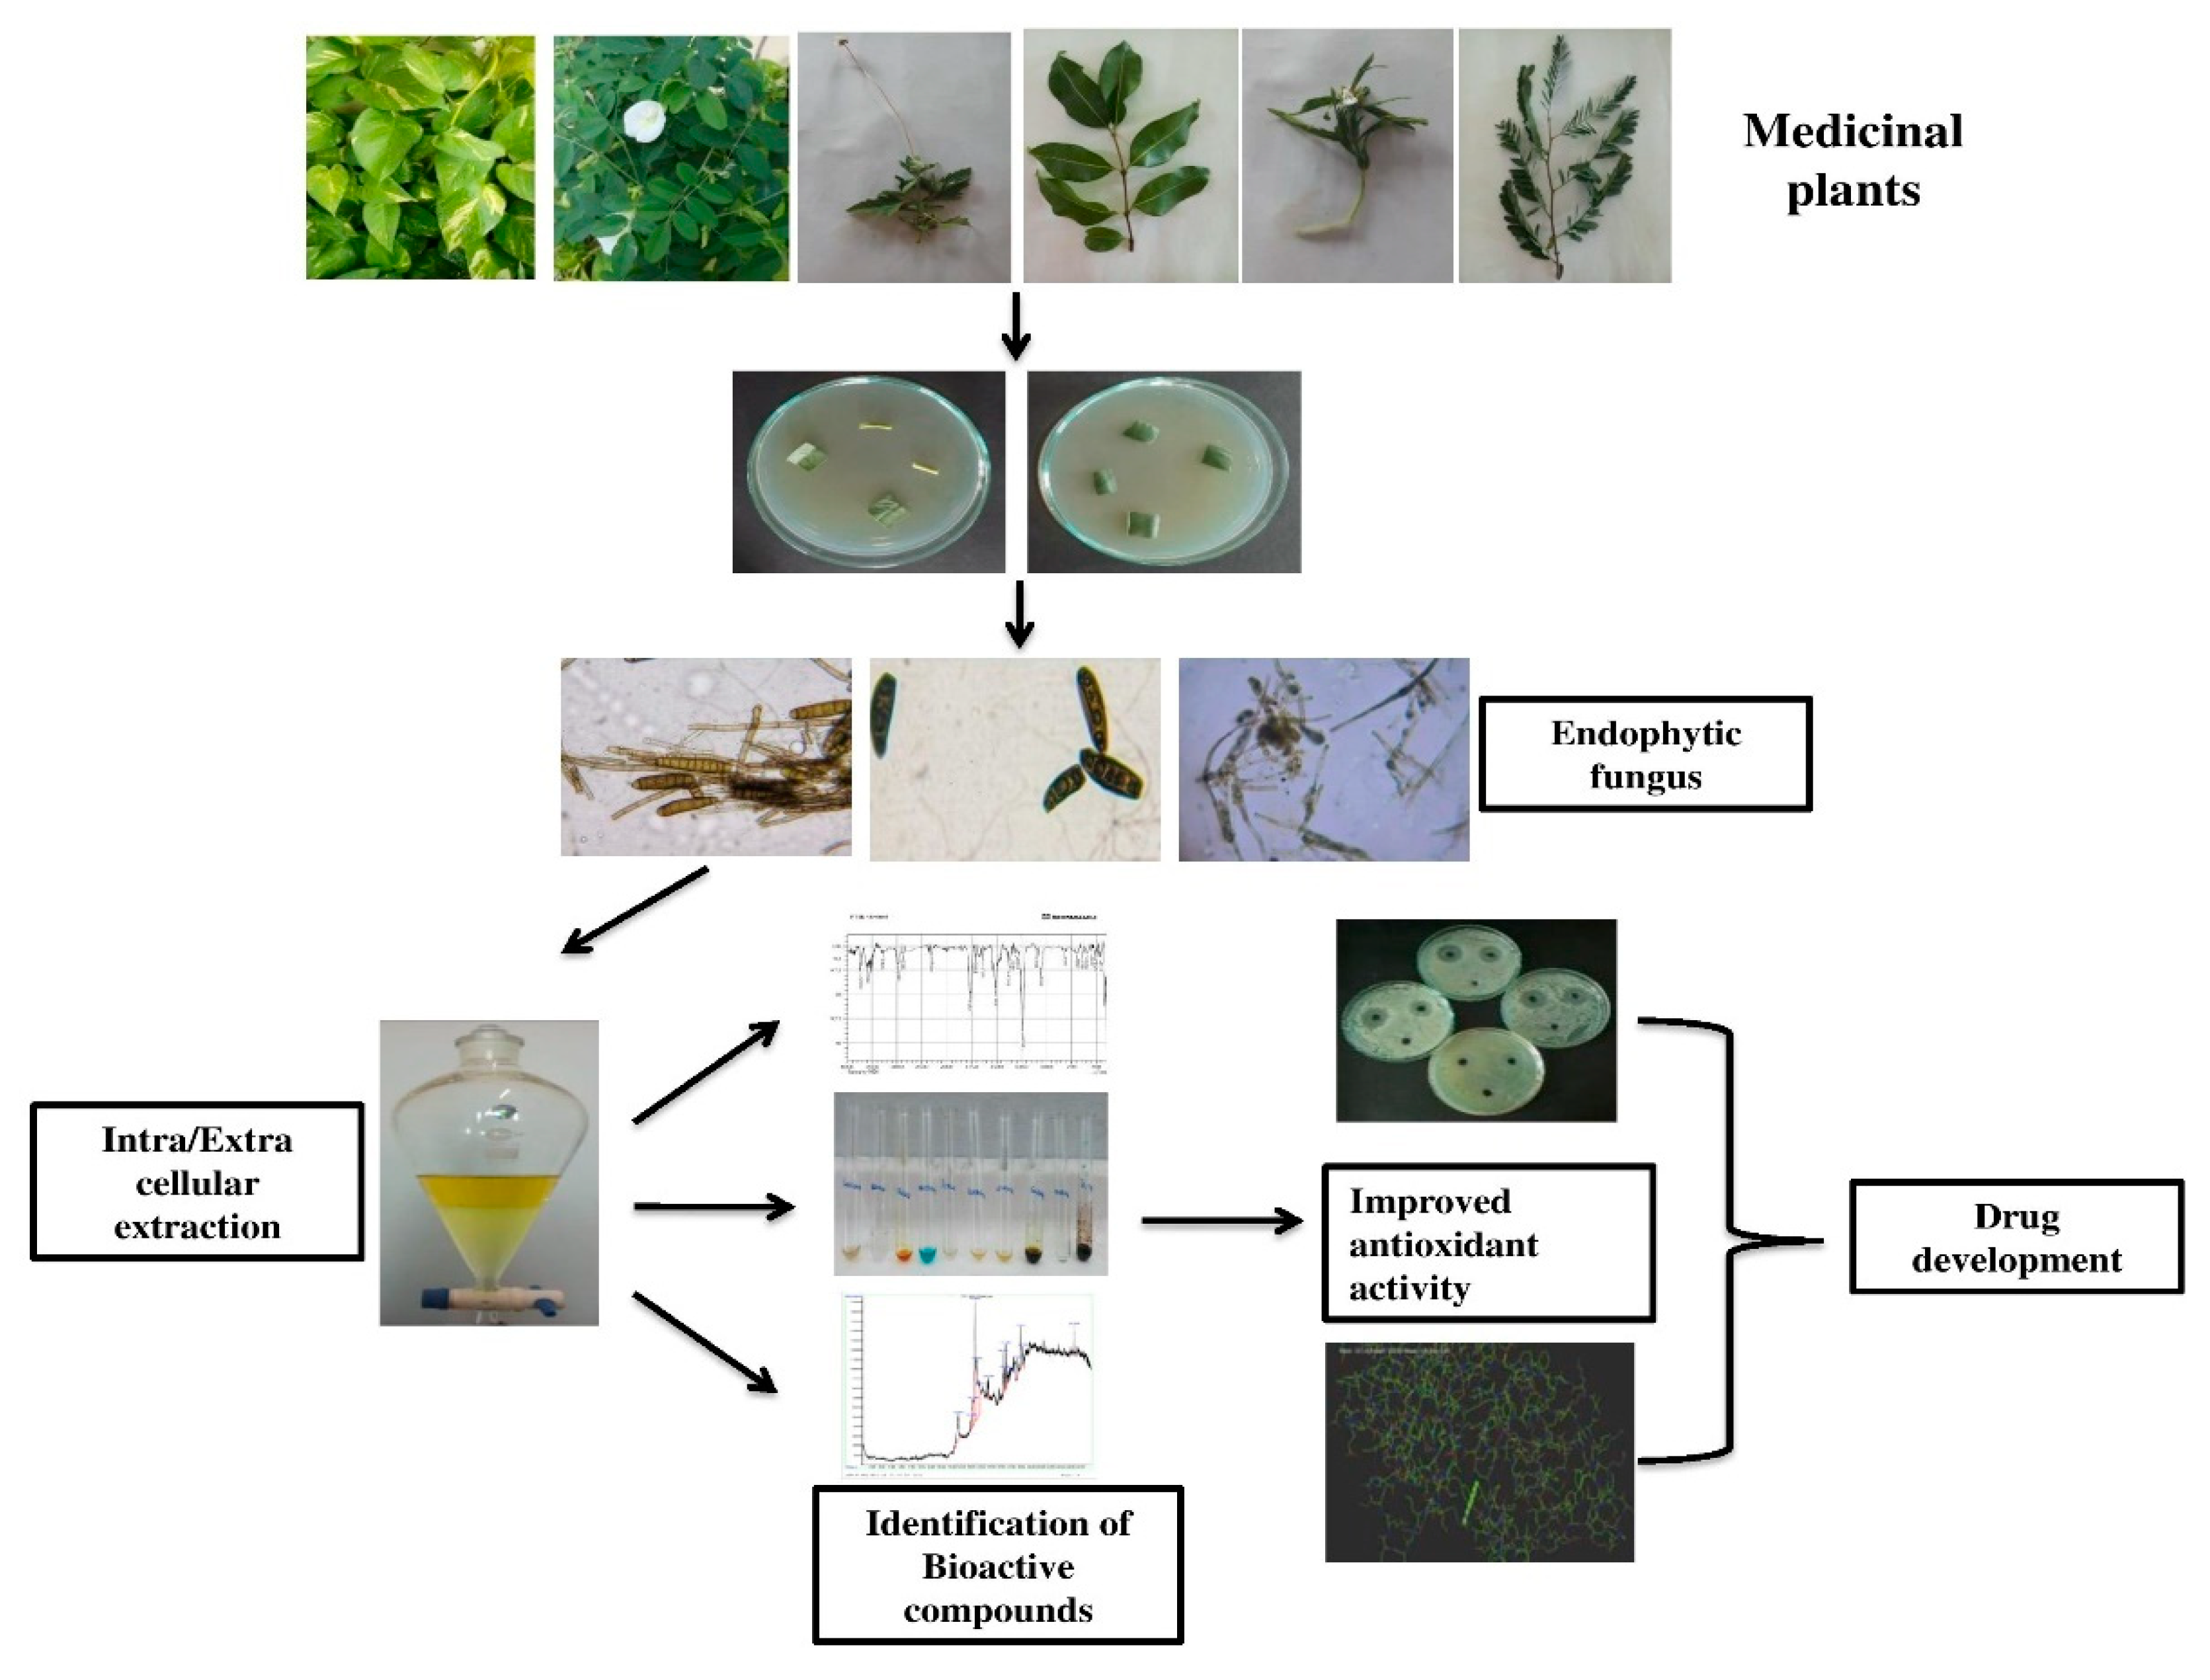

Bioactive Components and Health Potential of Endophytic Micro-Fungal Diversity in Medicinal Plants

Abstract

3. Results and Discussion

3.1. Endophytic Microfungal Isolation